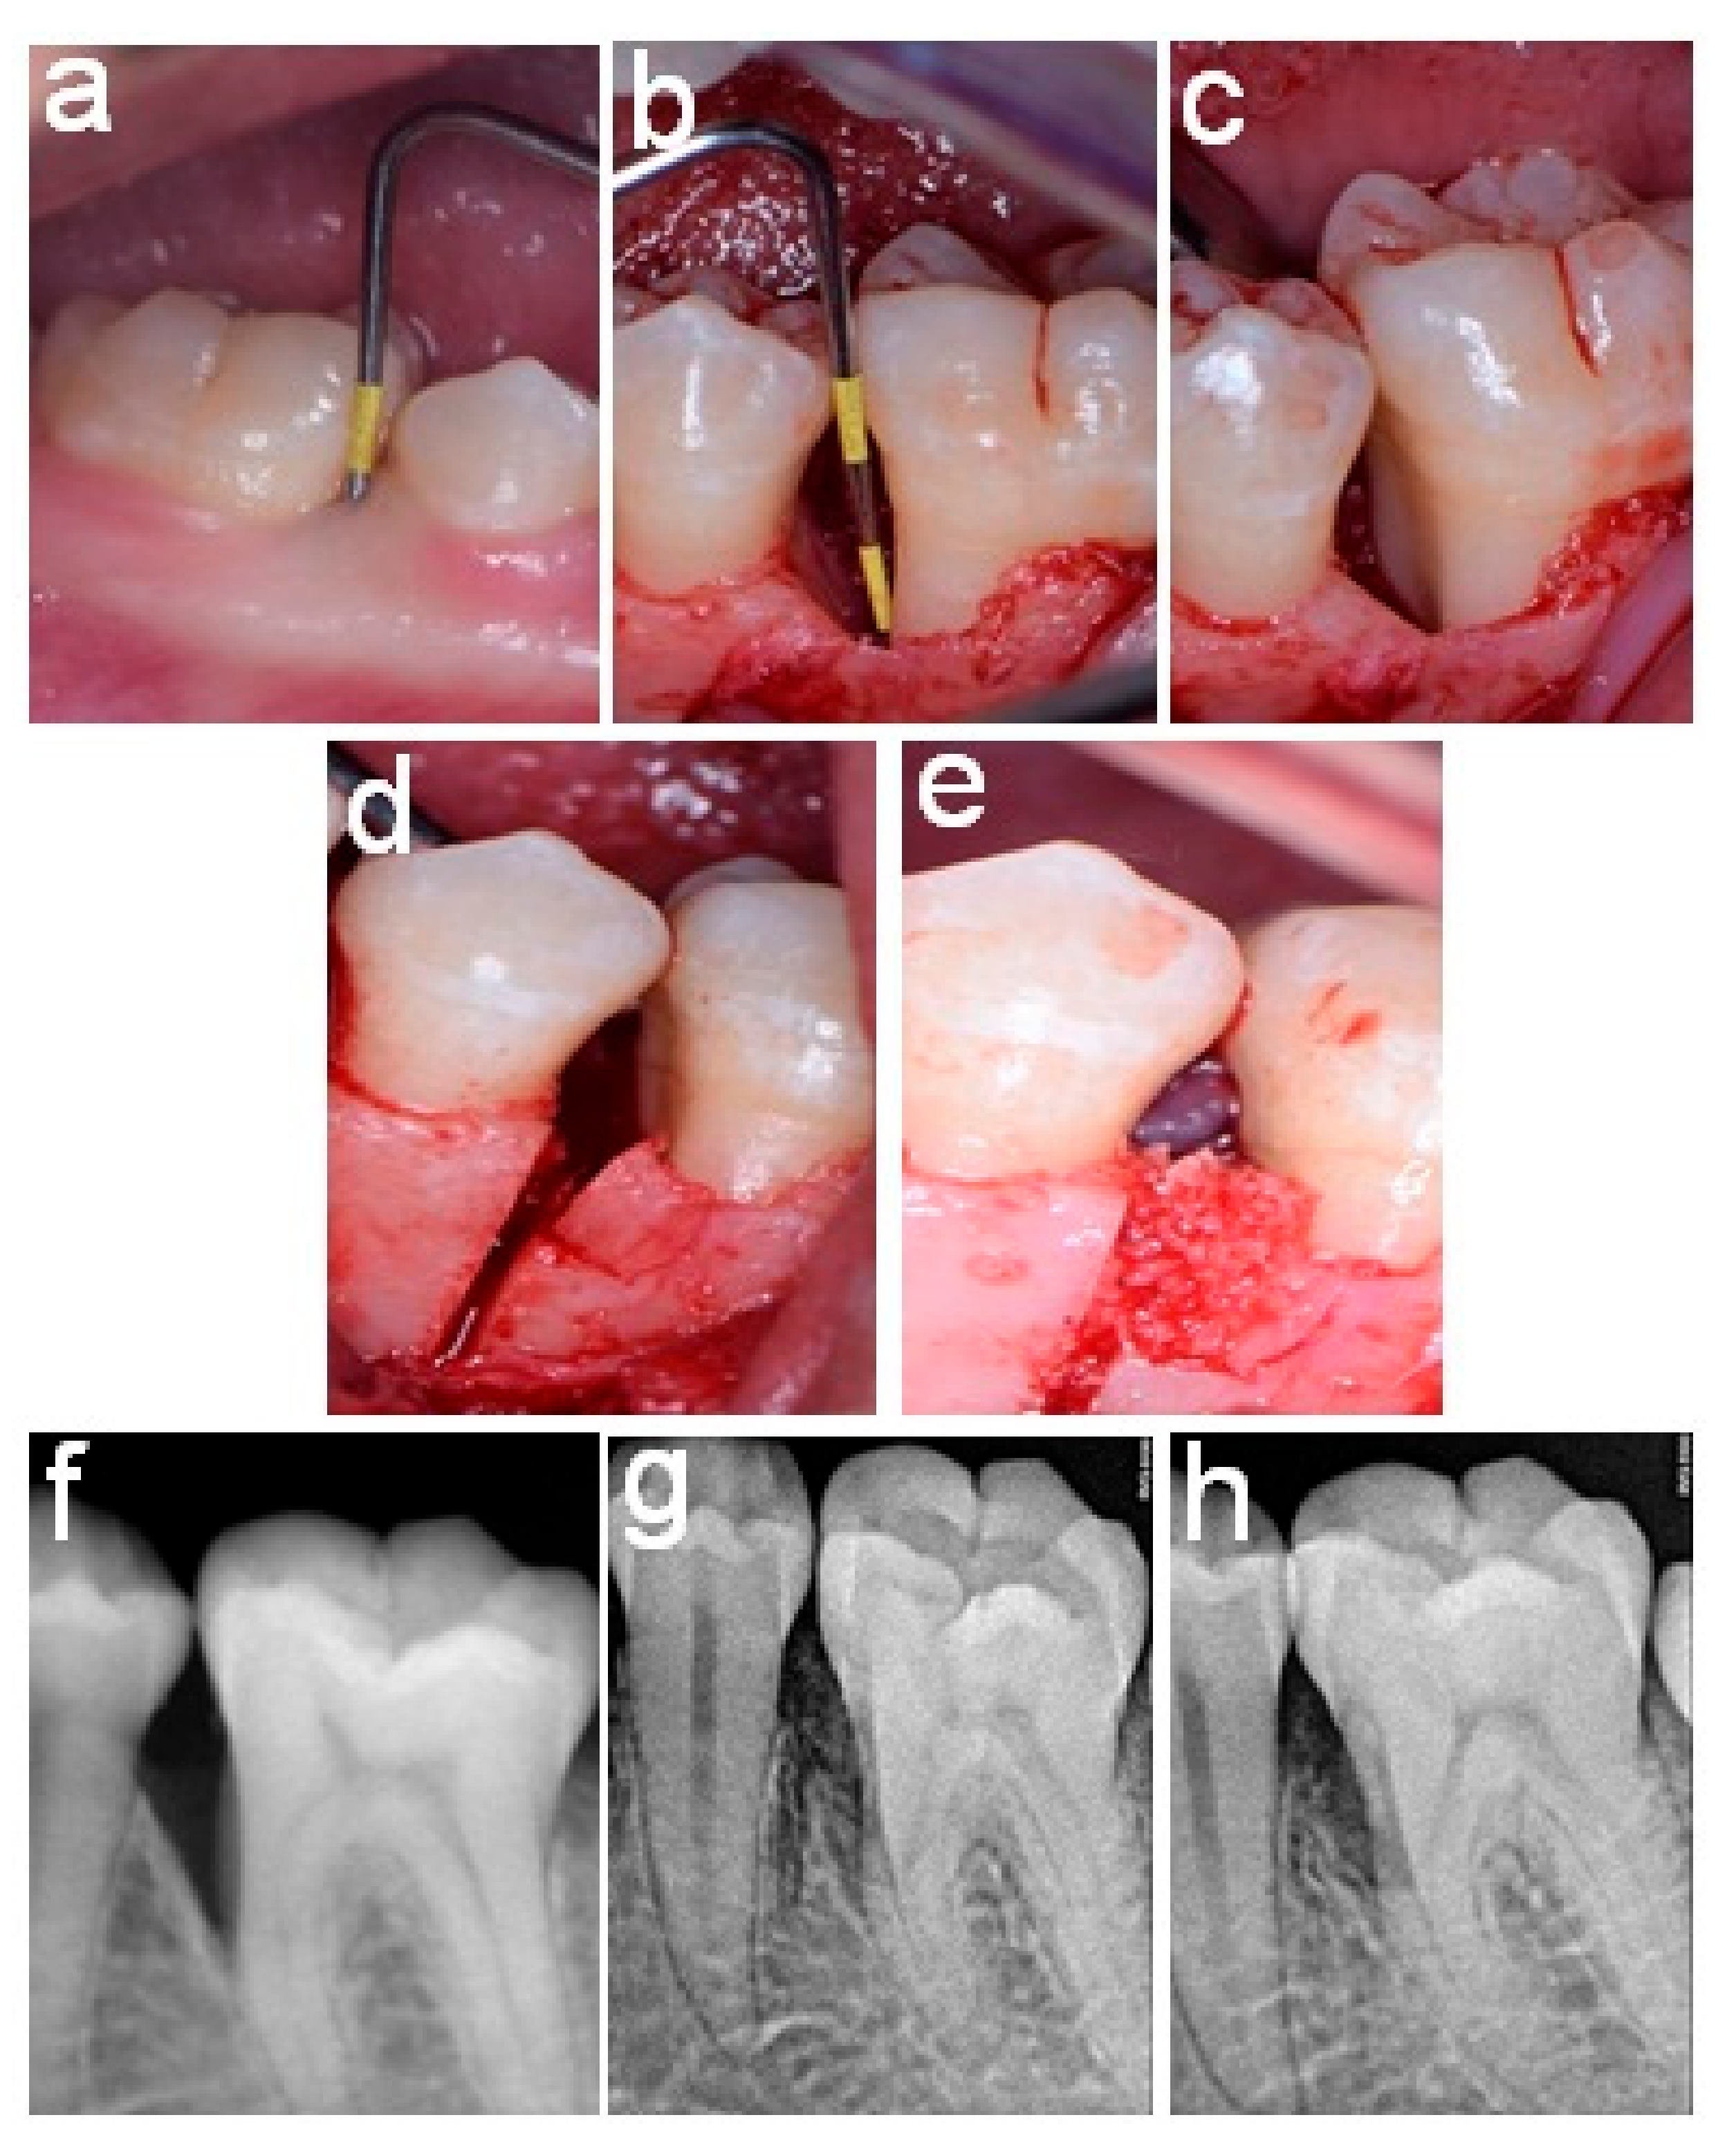

2.4. Surgical Procedures